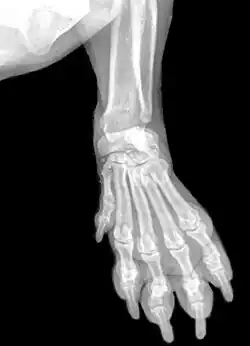

Передняя лапа собаки (такса)